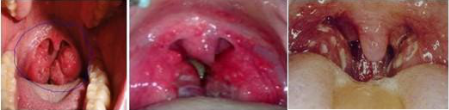

2、很多家庭选择在春节吃火锅,美味且适合节日的喜庆,但是吃火锅时,过热的食物和辣椒会刺激咽喉,啤酒里所含的一氧化碳还会加重对黏膜的刺激,这样的刺激久了,会诱发急性咽喉炎等咽喉疾病。

3、很多人会在酒足饭饱后去唱卡拉OK,或是一边K歌一边狂饮,其实,这样对嗓子非常不利。饭后大力唱歌刺激咽喉易发急性咽喉、声带异常等,因为酒精会对喉咙声带产生不小的刺激,使咽喉充血、肿胀,声音就会变得沙哑。